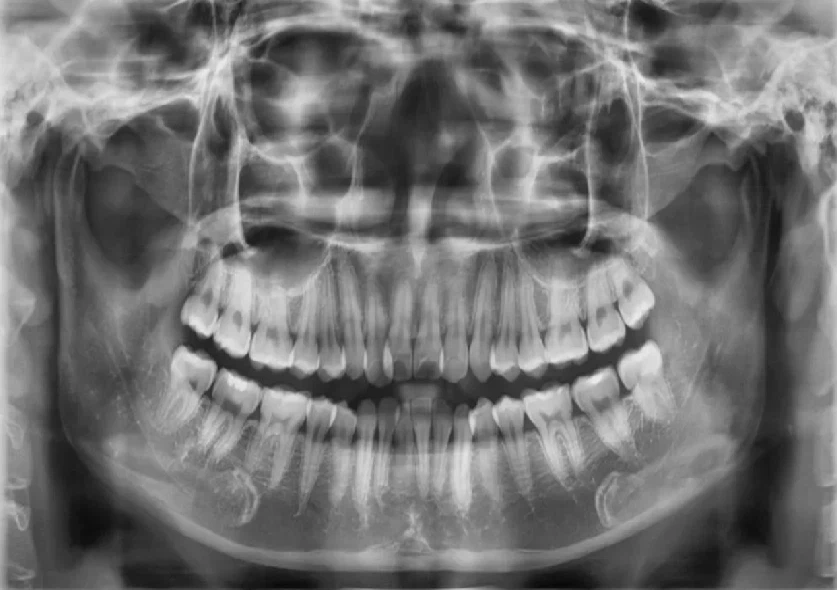

Bước 1: Thăm khám và tư vấn trực tiếp với bác sĩ chuyên cấy Implant

Bệnh nhân hỏng răng/mất răng khi có nhu cầu tìm lại hàm răng chắc khỏe bằng phương pháp cấy implant toàn hàm all on sẽ được thăm khám cùng bác sĩ một cách chi tiết, tỉ mỉ sau đó chụp phim CT ConeBeam. Khi có phim chụp X-quang, bác sĩ sẽ đánh giá mật độ xương hàm và lựa chọn số lượng trụ Implant phù hợp với tình trạng của bệnh nhân.

Kết quả chụp CT ConeBeam